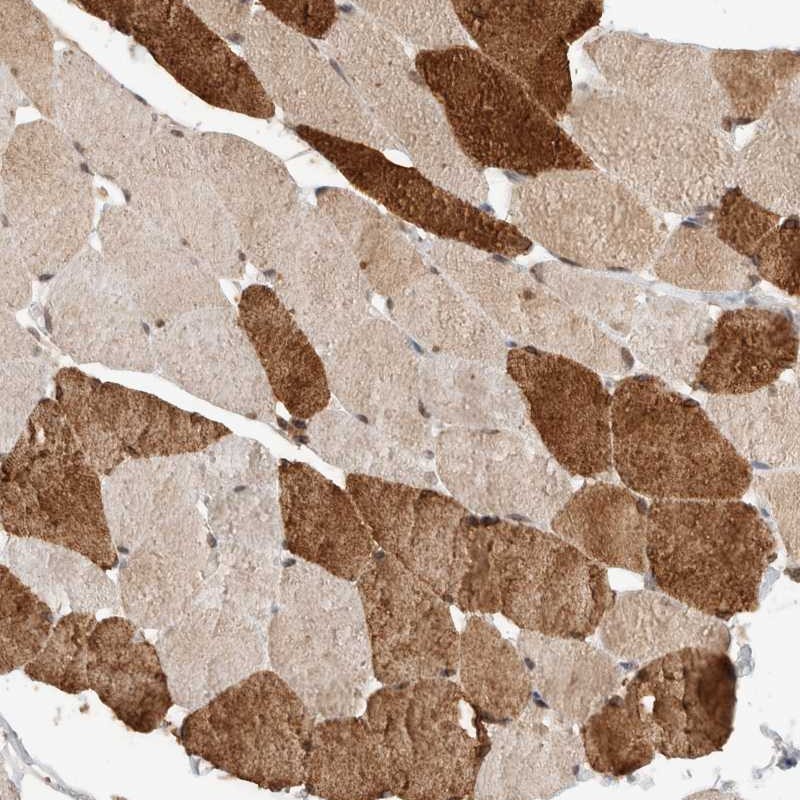

Immunohistochemical staining of human skeletal muscle shows strong cytoplasmic positivity in subsets of muscle fibers.